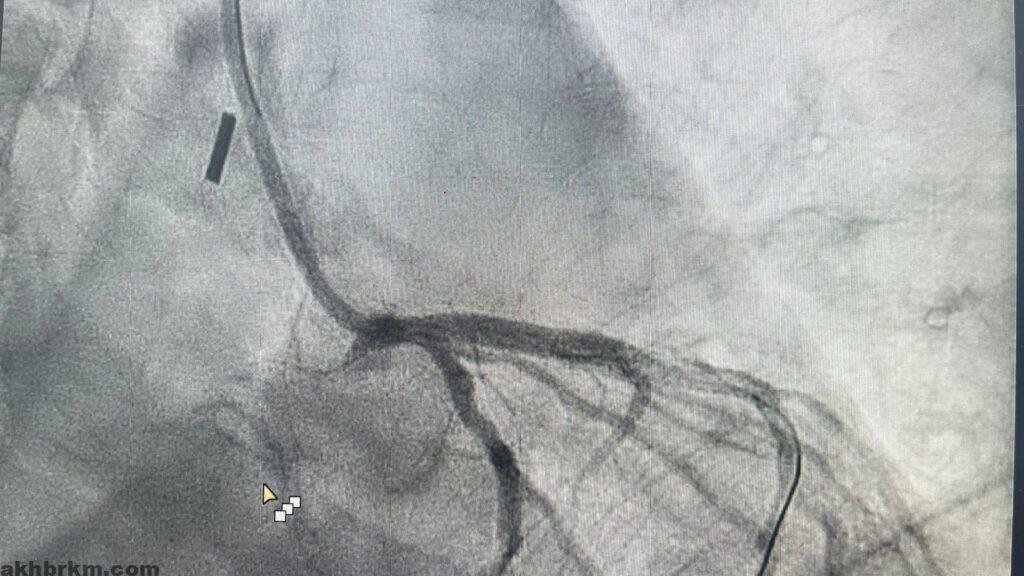

وقال الفريق الطبي المعالج بأنه بعد تفعيل مسار الجلطات القلبية ووصول الفريق الطبي من قسم القسطرة القلبية تم التعامل مع المريض وتبين أن هناك تضيق شديد بنسبة ٩٩ ٪ في الشريان الأيسر الرئيسي كاد أن يودي بحياة المريض ، حيث ان هذا الشريان يغذي ٧٠٪ من عضلة القلب ويحتاج الى تدخل جراحي عاجل لزراعة الشرايين “عملية قلب مفتوح”.

وأشار الفريق الطبي بأنه تم خلال القسطرة وضع مضخة داعمة للدورة الدموية في الشريان الأبهري لتحسين كفاءة عضلة القلب ووضع دعامة لفتح الشريان وتحسين تدفق الدم للعضلة واستقرار حالة المريض وتكللت ولله الحمد بالنجاح وتم متابعة حالة المريض وقد خرج في اليوم التالي.